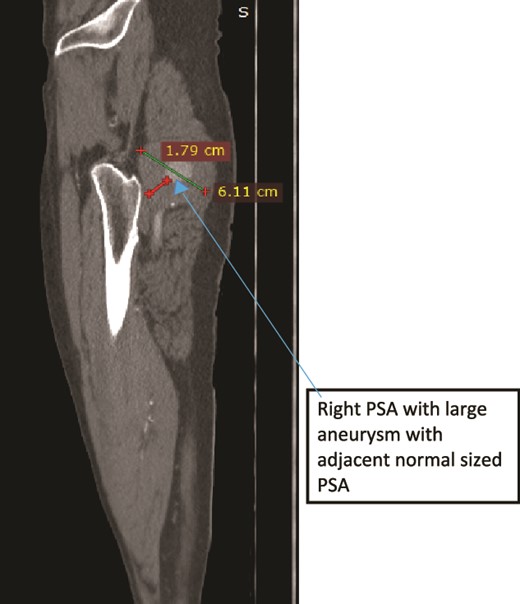

Case 2—sagittal images of LL CTA of the right LL arteries showing large aneurysm with surrounding thrombus with adjacent normal-sized PSA.